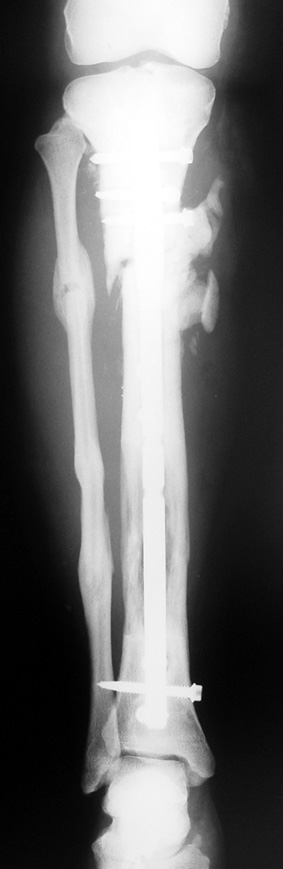

The duration of external fixation (external fixation index) depends on the amount of distraction required, and the extremity is prone to complications during this period. After the distraction phase is completed, the external fixator remains in place during the consolidation phase, which lasts twice as long as the distraction phase; but this period is hardly tolerated. If the external fixator is removed before sufficient consolidation is achieved, fractures, deformity and shortness will be the result. In our department, ‘lenghthening over nail’ method is used in order to decrease the external fixation index and increase patient comfort and activity level. In this method, the intramedullary nail is statically locked after the completion of the distraction phase, and external fixator is removed. The extremity is stabilized by the intramedullary nail during consolidation phase. In this way, complications due to long external fixation index or early removal of the external fixator are avoided.

Case 1